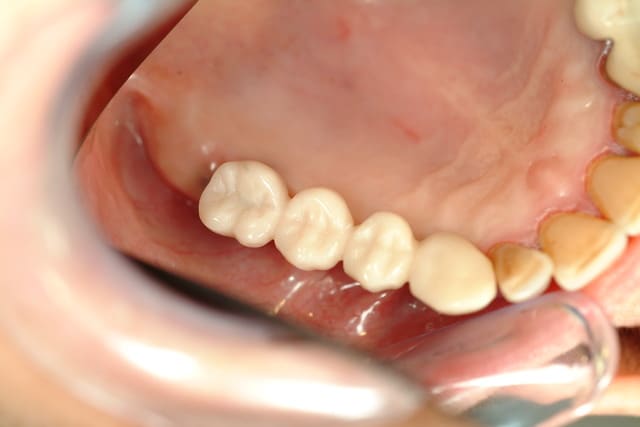

Bonjour Céramik,

Je suis de l'avis de Pxav, concernant l'expansion, il faut voir le scan et la hauteur d'os disponible.

Expansion tout à fait envisageable et pose d'implants coniques de 3,3 à 3,75 max de Diam.

A mon sens, Il y'a également la possibilité de poser des implants monobloc de 3 à 3,6 de diam beaucoup plus fins que des implants à hexagone interne de 3,3 de diam, mais attention aux axes.

je pense que dans ces cas, il ne faut pas écarter ce type d'option qui rend de très grands services aux patients et au praticien.

Pour des implants monoblocs, expansion minimum, puisque le forage se fait à 2 mm et 2,5 uniquement pour la corticale.

Depuis 4 à 5 ans je traite de façon plus simple ce type de cas, ils sont gérés très rapidement avec des implants une pièce.

Les taux de réussite et d'acceptation de traitement (beaucoup plus courts) sont aussi plus importants.

Quasiment aucune morbidité par rapport aux greffes osseuses.

Il serait bon de confirmer avec le Scan.

Pour info, voici quelques cas traités avec ces implants Monobloc.